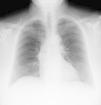

A postoperative chest X-ray was taken at ICU admission (Fig. 1), which revealed a marked right-displacement of the trachea and an increased density area in the mediastinum, which was identified as a hematoma caused by the catheter placement. None of these findings were present in the preoperative chest X-ray (Fig. 2). A computed tomography and thoracic angiography (Fig. 3) were performed and neither active bleeding nor airway compromise was found. The catheter was removed without complications. One week later chest X-ray showed no alterations.